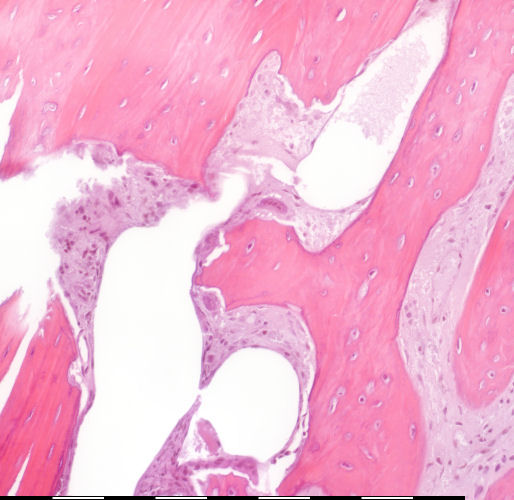

Medium magnification of immature bone

Lakuna in resorpsie sone / Eroded lacuna Osteosiete / Osteocytes Osteoblaste / Osteoblasts Endosteale selle / Endosteal cells Groeilyne / Growth reversal lines Howship lakunae / Howship lacunae Osteoklaste / Osteoclasts